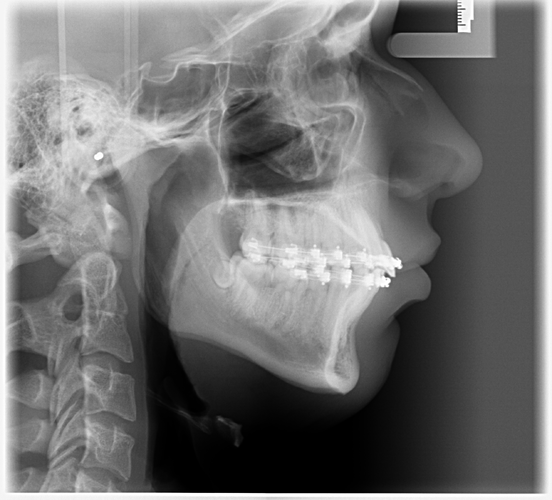

I had Bimaxsurgery + genioplasty yesterday performed by Dr Dr Kater, Frankfurt am Main, Germany. I'm 17 and it went well, no nerves are botched and he told me the Plan was executed perfectly fine. In the pictures you can see 24h before and 24h after the surgery. He did a great job with my maxilla and mandible but the genioplasty is slightly underadvanced. My nose had a very big glowup but it'll all look different in 5 months i'm very bloated rn. What do yall think?